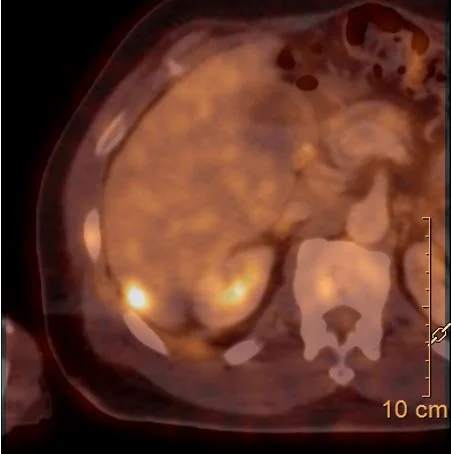

Hypermetabolic on PET/CT.